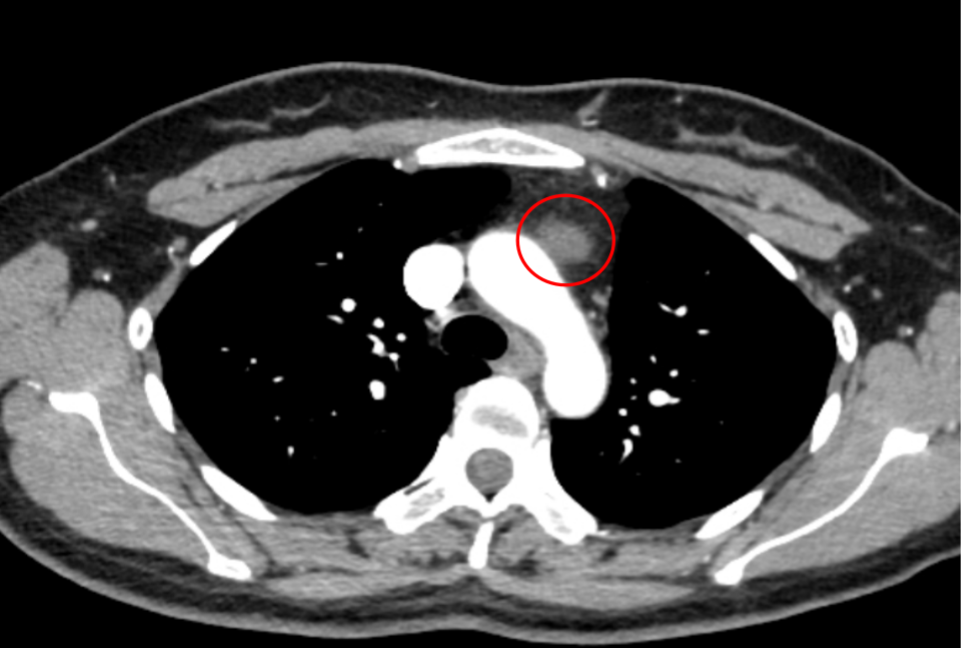

患者為年輕女性,14 年前曾因左下肺支擴(kuò)伴不張接受左下肺葉切除術(shù),2 年前復(fù)查時(shí)發(fā)現(xiàn)左前縱隔占位及右上肺磨玻璃結(jié)節(jié)。隨訪(fǎng)兩者均增大,考慮胸腺腫瘤及右上肺早癌可能,需盡快手術(shù)治療。但由于患者縱隔腫物位于左前縱隔,且合并右上肺病灶,若采用傳統(tǒng)側(cè)胸入路,難以同時(shí)完成兩處病灶切除,手術(shù)難度極大。

陳新富主任團(tuán)隊(duì)對(duì)患者病情進(jìn)行充分細(xì)致的術(shù)前討論,綜合評(píng)估病灶位置、既往手術(shù)史及身體狀況后,決定采用劍突下入路為患者實(shí)施“全胸腺切除 + 右上肺結(jié)節(jié)切除”術(shù),手術(shù)過(guò)程流暢順利。患者術(shù)后第二天即拔除胸管,下床活動(dòng)。